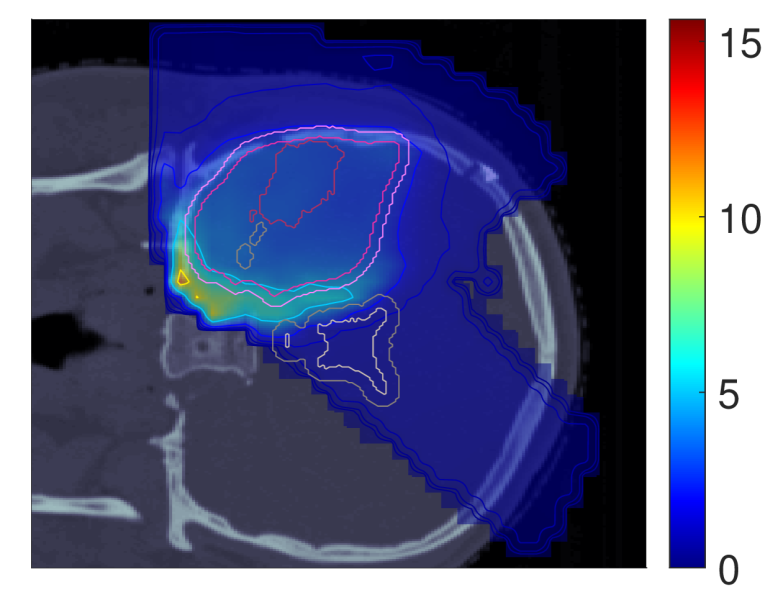

In light of the dose distribution changes and the interdependency between dose and dose-averaged LET, we can identify patterns in the slice images with the optimal dose-averaged LET distributions shown in Figure 5.

NTCP30 %NTCP\approx{$30\text{\,}\mathrm{\char 37\relax}$} NTCP20 %NTCP\approx{$20\text{\,}\mathrm{\char 37\relax}$} NTCP10 %NTCP\approx{$10\text{\,}\mathrm{\char 37\relax}$}

ldl_{d} (NTCPp)(NTCP_{p})

Refer to caption Refer to caption Refer to caption

ldl_{d} (LSEp~)(LSE_{\tilde{p}})

ldl_{d} (H~p)(\tilde{H}_{p})

ldl_{d} (H~p~)(\tilde{H}_{\tilde{p}})

Figure 5: Optimal slice images of the dose-averaged linear energy transfer ldl_{d} (in keV/μ\boldsymbol{\mu}m) for NTCPpNTCP_{p}, LSEp~LSE_{\tilde{p}}, H~p\tilde{H}_{p} and H~p~\tilde{H}_{\tilde{p}} at different NTCP levels. The shifts in ldl_{d} coincide with those observed on the slice images for dRBE,fxd_{RBE,fx}, i.e., there seems to be a trade-off between dRBE,fxd_{RBE,fx} and ldl_{d} that is consistent with the mathematical structure of the POLO model. As a result, the ldl_{d} slice images for NTCPpNTCP_{p} and H~p\tilde{H}_{p} are almost equivalent, while LSEp~LSE_{\tilde{p}} and H~p~\tilde{H}_{\tilde{p}} differ. For the latter two objective functions, the shift of dRBE,fxd_{RBE,fx} outside the target volume appears to be crucial, or, respectively, no shift of ldl_{d} is necessary due to the strength of the reduction of dRBE,fxd_{RBE,fx}.

First, we note that ldl_{d} hotspots do not manifest in the high dose regions – this would be a risk driver because of the product term in the POLO model from Section II.A. Generally, some trade-off between dRBE,fxd_{RBE,fx} and ldl_{d} is evident, where the optimizer allows for higher values of ldl_{d} when dRBE,fxd_{RBE,fx} has been sufficiently reduced, and vice versa.

For NTCPpNTCP_{p}, the slight reduction of dRBE,fxd_{RBE,fx} outside the target volume coincides with a redistribution of ldl_{d}: higher values in the target volume are prevented, and instead induced along the margins of the PTV. Once again, H~p\tilde{H}_{p} behaves almost identically. Following the dose/LET trade-off, the almost unchanged values for LSEp~LSE_{\tilde{p}} can also be explained: LSEp~LSE_{\tilde{p}} minimally reduces dRBE,fxd_{RBE,fx} in the region of overlap with the VS, meaning that high ldl_{d} values there would be detrimental to the outcome prediction. Consequently, ldl_{d} could only approach the “dose gap” that opens up within the target volume, or remain constant while the shifts in the dose distribution account for the reduction in NTCP.

Finally, for H~p~\tilde{H}_{\tilde{p}}, we observe a sharp envelopment of the lower side of the PTV margin, consistent with the fall-off in dRBE,fxd_{RBE,fx} there. At an NTCP level of 10 %10\text{\,}\mathrm{\char 37\relax}, the high ldl_{d} region has virtually manifested itself with hot spots partially overlapping the VS. However, revisiting the slice image for dRBE,fxd_{RBE,fx}, this is not surprising, as in addition to the lower values in the target volume, the dissipation of dRBE,fxd_{RBE,fx} to the outside is only enhanced towards the upper end, leaving space for the ldl_{d} band on the lower end, between the PTV margin and the VS.

Again, we can confirm the slice images by the LET-volume histograms (LET-VHs) from Figure 6. For NTCPpNTCP_{p} and H~p\tilde{H}_{p}, the values decrease with lower NTCP for all VOIs. LSEp~LSE_{\tilde{p}} almost does not change the distributions, only a slight increase at the left margin of the target volume is visible both in the slice images and in the respective LET-VH curves. Meanwhile, H~p~\tilde{H}_{\tilde{p}} reduces the values in all VOIs, just as NTCPpNTCP_{p} and H~p\tilde{H}_{p}, but in contrast, for the VS, the lower range is more attenuated and the upper range is enriched due to the redistribution along the PTV margin.